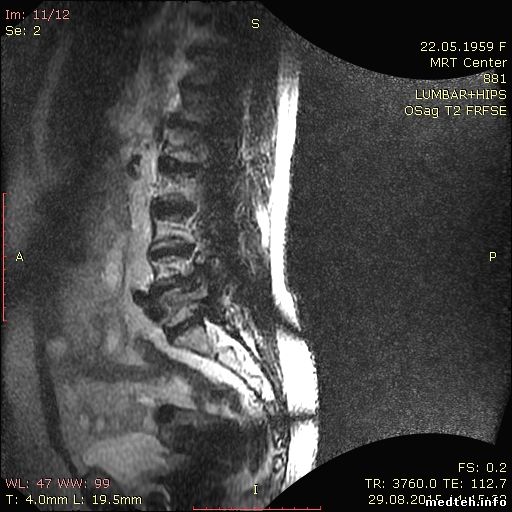

МРТ GE Signa Profile 0,2T 2007г выпуска. При сканировании грудного или поясничного отдела позвоночника на катушках BODY и CTL, только на последовательности Т2 Sag, появляются помехи на изображении в виде дуги.

Может кто подскажет, с чем это может быть связано? Может кто сталкивался с такой проблемой.

я не имел дела с GE, но такая "дуга" очень похожа нарушение работы одной из градиентных катушек, я бы даже сказал, что это Z-гадиент

slaval, это у вас, скорее всего, просто край катушки или проблемы с однородностью B1.

Проверьте, что у вас исследуемая область находится в центре поля сканирования - уж очень крутая дисторсия на картинках.

Elya, посмотрите на то, как выглядит край приемной зоны на CP Extremity. Очень похоже. Градиенты тут вообще не при делах.

извиняюсь, попутал.. неполадки с градиентами глобально влияют на картинку, а здесь точно что-то с областью сканирования, наложение срезов получается